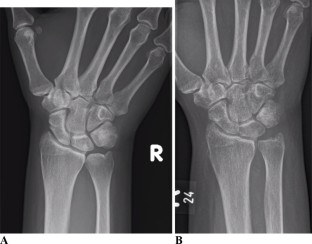

Fig. 1